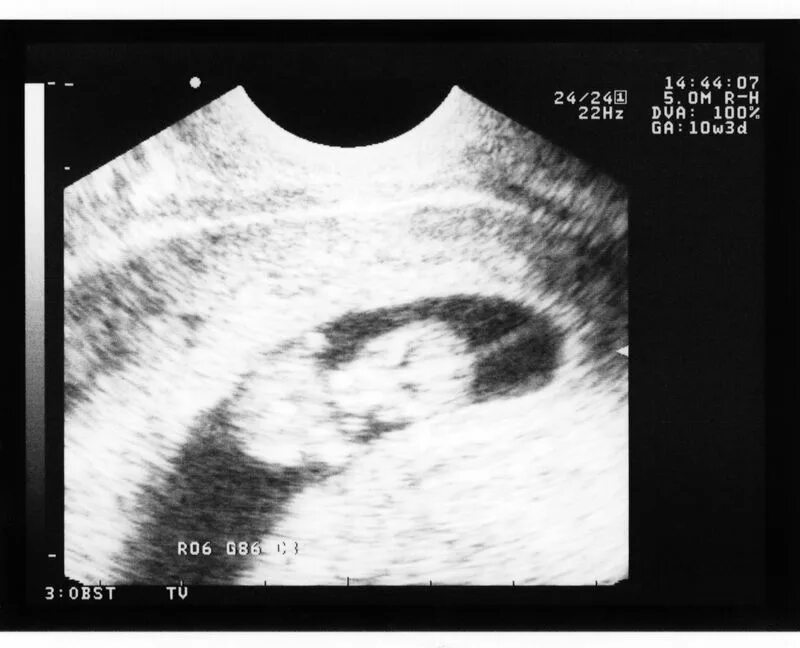

Можно ли забеременеть при загибе матки